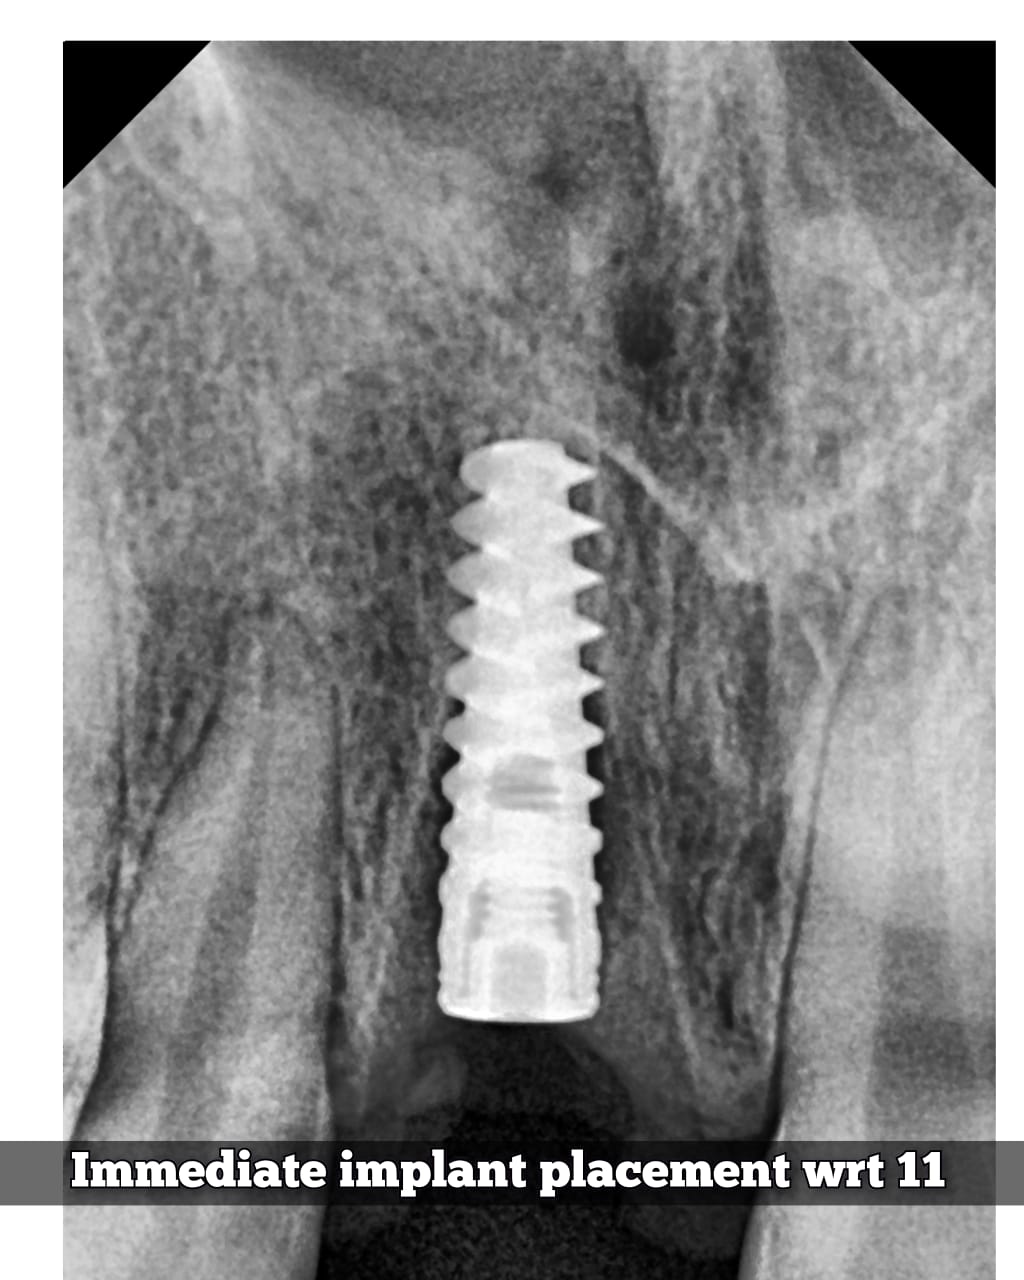

Photo Gallery